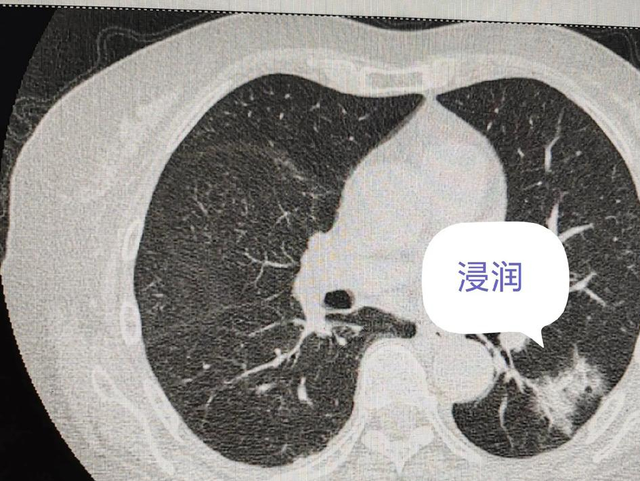

肺部结节是指肺部实质内直径小于或等于3厘米的、近似圆形的、边界相对清晰的密度增高影。当肺部出现两个或两个以上的结节时,即称为肺部多发结节。

常见的病因包括:感染性疾病(如结核、真菌感染等)、炎症反应(如肉芽肿、风湿性疾病等)、良性肿瘤、恶性肿瘤以及其他病因(如血管畸形、肺内淋巴结等)。

值得注意的是,虽然恶性肿瘤是引起肺部结节的重要原因之一,但并非所有多发结节都意味着恶性,尤其是当结节较小、数量较多且分布有规律时,往往提示良性可能性较大。

第二,结节的形态。边缘光滑、圆形或椭圆形的结节多为良性;而边缘毛刺、分叶、不规则形态的结节则需要警惕恶性可能。

第三,结节的密度。纯磨玻璃密度(GGO)、混合密度的结节恶性可能性较高,而钙化、脂肪密度的结节多为良性。

第五,结节的数量和分布。多发性、双肺分布、随支气管血管束分布的结节多为良性或转移瘤;而单个、孤立的结节则需警惕原发性肺癌可能。